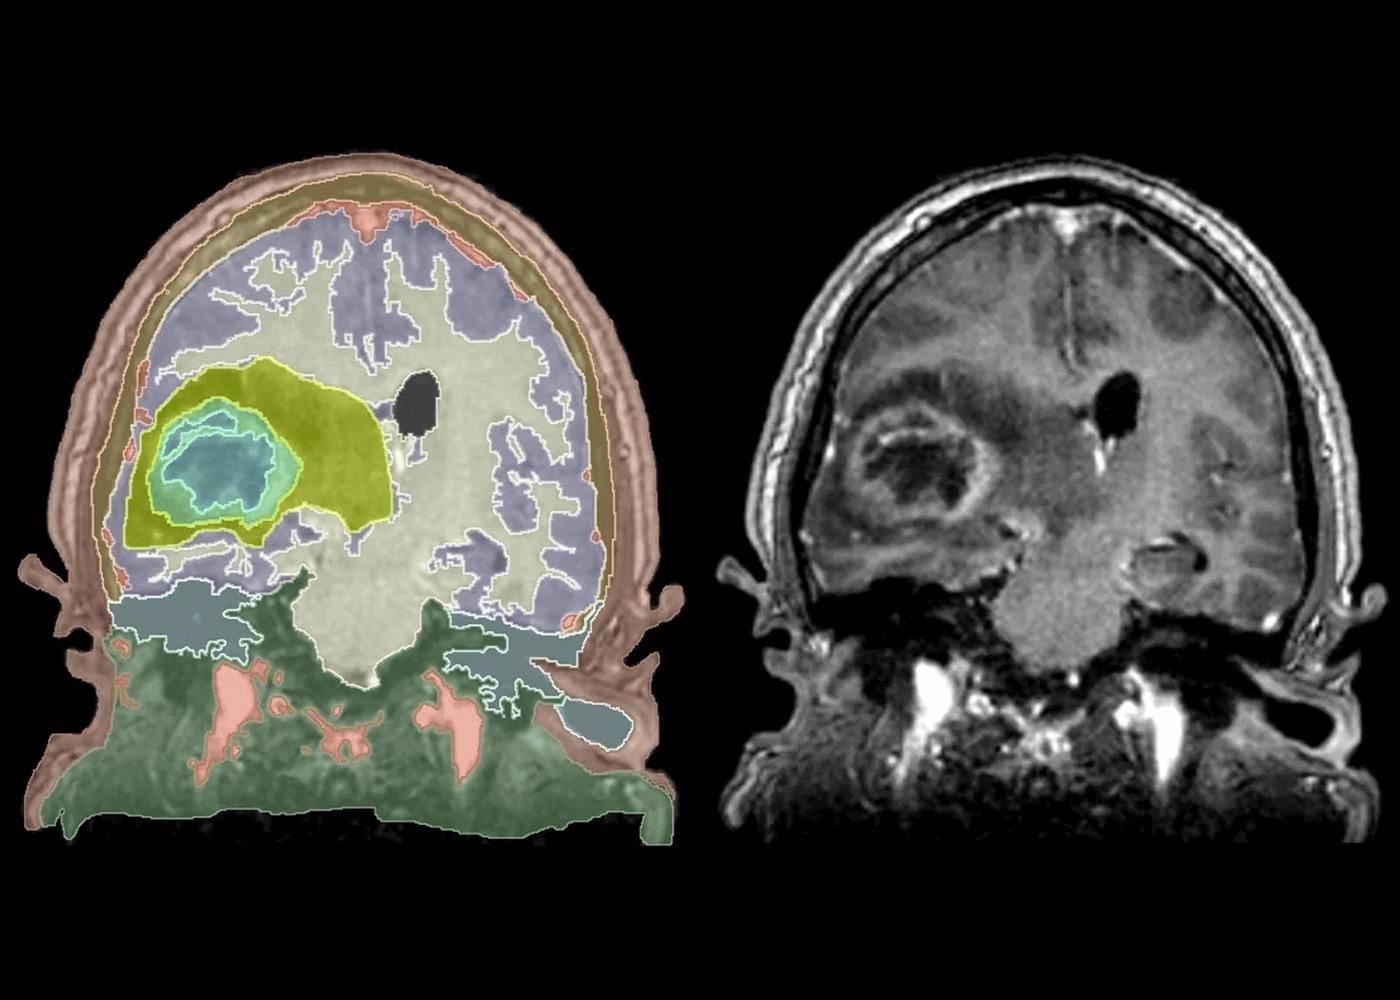

radiology

Brain tumor and anatomical structures segmentation

Brain Tumor: radiology labeling on 3D Slicer